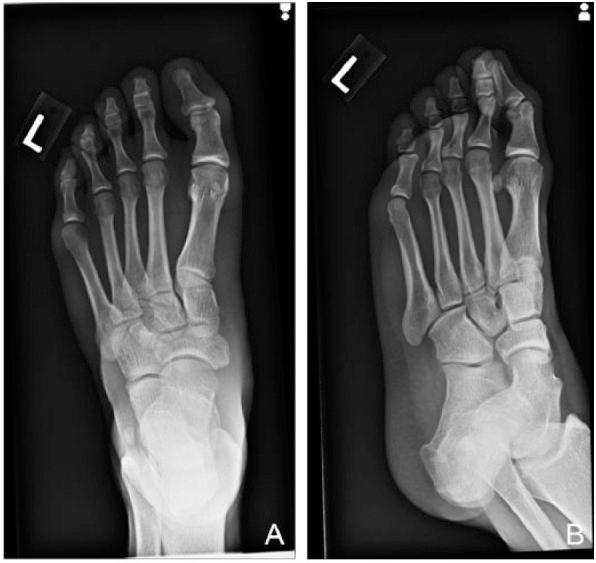

Dancers frequently present to the sports medicine clinic with a variety of lower extremity complaints ranging from acute and traumatic injuries to more chronic, overuse injuries. This case series depicts a similar and unique incidental radiographic finding found in 2 young dancers seen at the same sports medicine clinic. While the findings are likely benign and unrelated to both patients' initial presentation, the finding of acroosteolysis can be found in more serious systemic and genetic processes as well an early finding in repetitive trauma.

舞者经常因各种下肢问题前往运动医学诊所就诊,这些问题涵盖从急性创伤性损伤到更慢性的过度使用损伤。本病例系列描述了在同一家运动医学诊所就诊的两名年轻舞者身上发现的一种相似且独特的偶然影像学表现。虽然这些表现可能是良性的,且与两位患者最初的症状无关,但肢端骨质溶解也可能出现在更严重的全身性和遗传性疾病过程中,以及重复性创伤的早期表现中。